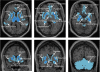

Main results of the radioactivity peak analysis (n = 14). A peak analysis identified brain regions with high radioactivity counts in PET images including (A) striatal areas, (B) thalamus and hippocampus, (C) midbrain and (D) temporal cortex. Note the decrease in intensity threshold necessary to identify peaks (dark red, arrows) in extrastriatal regions (color bar on right side of each PET image). Mean PET counts in the cerebellar reference region was 1.